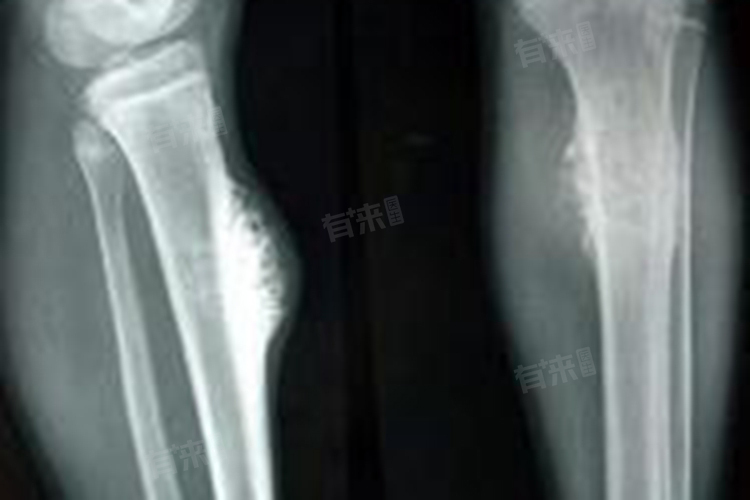

3、病理性骨折:骨癌会破坏骨骼的正常结构,使其强度降低,轻微外力作用下就可能发生骨折,这被称为病理性骨折。肿瘤细胞侵蚀骨质,导致骨小梁破坏、骨皮质变薄,骨骼难以承受正常的生理应力。如在椎体骨癌患者中,可能因轻微的弯腰、咳嗽等动作引发椎体压缩性骨折,导致背部剧烈疼痛,甚至出现脊柱畸形。